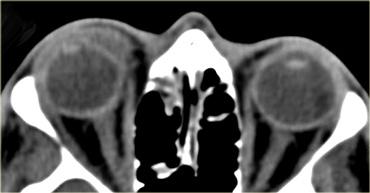

Bệnh mắt tuyến giáp

Hãy quan sát các hình ảnh bên trái, mô tả chúng và đưa ra chẩn đoán phân biệt, đồng thời tạm thời bỏ qua tiêu đề của đoạn này.

Chẩn đoán là bệnh mắt tuyến giáp và chẩn đoán phân biệt là giả u hốc mắt.

Chúng ta sẽ thảo luận ngay sau đây về cách phân biệt hai bệnh lý này.

Trước đây, thuật ngữ bệnh nhãn khoa Graves được sử dụng.

Tuy nhiên, điều này gợi ý rằng bệnh nhân đang trong tình trạng cường giáp.

Ngày nay, chúng ta biết rằng những bệnh nhân được điều trị bệnh Graves có thể có chức năng tuyến giáp bình thường hoặc thậm chí suy giáp mà vẫn có thể phát triển bệnh mắt tuyến giáp, do đó hiện nay chúng ta sử dụng thuật ngữ bệnh mắt tuyến giáp.

Nguy cơ lớn nhất của bệnh mắt tuyến giáp là bệnh lý thần kinh thị giác do chèn ép, có thể do chèn ép trực tiếp bởi các cơ hoặc do thiếu máu cục bộ gây ra bởi sự chèn ép các mạch máu.

Đặc điểm then chốt cần tìm kiếm là đỉnh hốc mắt.

Nếu không thấy mô mỡ xung quanh đỉnh hốc mắt, khả năng cao có tình trạng chèn ép.

Những bệnh nhân này được điều trị bằng phẫu thuật giải áp qua nội soi, trong đó thành trong của hốc mắt (tức là lá giấy – lamina papyracea) được phá vỡ.Giả u

Bệnh có thể ảnh hưởng đến mọi thành phần của hốc mắt: cơ, gân, mô mỡ, thần kinh thị giác, bao thần kinh, tuyến lệ, v.v.Điểm phân biệt then chốt giữa giả u và bệnh mắt tuyến giáp là trong giả u, không chỉ các cơ mà cả các gân cũng bị tổn thương.

Những bệnh nhân này cảm thấy đau khi cử động mắt do các gân bị kích thích.

Trên hình ảnh bên trái ngoài cùng, hãy chú ý sự thon nhỏ dần của cơ bị phù nề tại điểm bám gân ở bệnh nhân mắc bệnh mắt tuyến giáp.

Bên cạnh đó là hình ảnh của bệnh nhân mắc giả u.

Hãy chú ý rằng tình trạng phù nề lan rộng đến tận điểm bám gân.Bệnh lý ngoài nón cơ